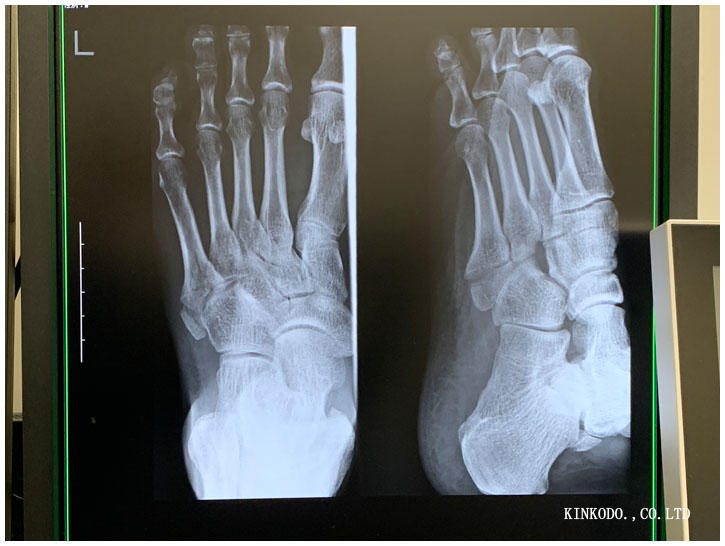

5時から骨折して四週間目の診察。今日は骨折した日、そして二週間後、そして4週間後のレントゲン撮影。

拡大すると。

先生にどこがどう折れているのですか?と聞くと。

ここ。ん?パックリじゃないですか?

そう、でもパックリ割れているから骨と骨とが接するところが多いから。その方がいい。右の方、上の方の骨が見えてきたら少しずつ走ってもいいんだけどな。

と若干だけどモヤモヤ骨が見えているか見えていないか分からないようなレントゲンを見つめながら。

完治3ヶ月覚悟しました。